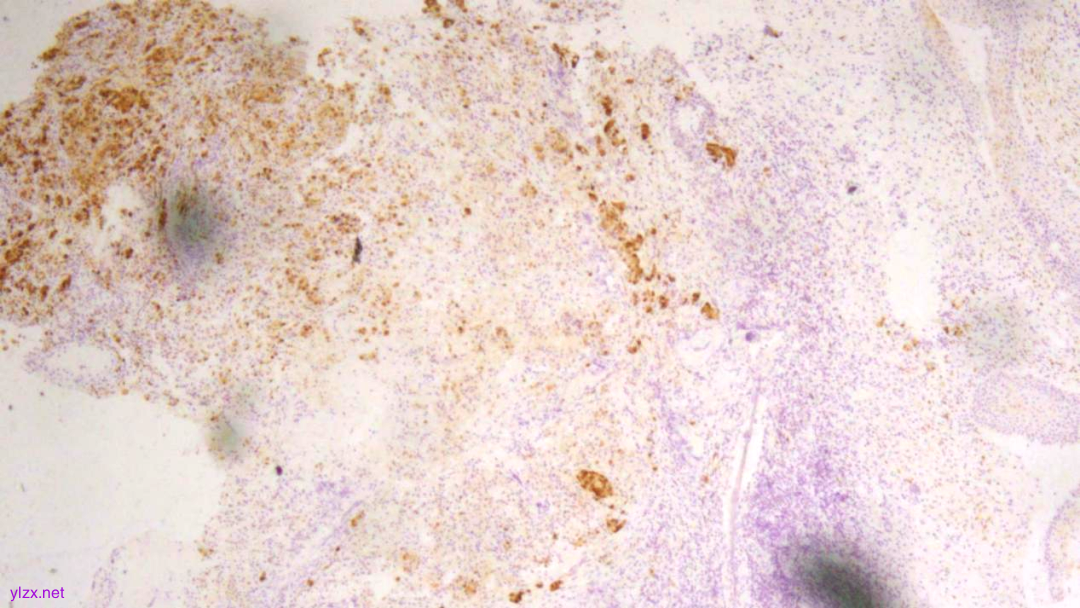

IHC结果:

P120(浆+),P16(灶+),P53(野生型表达),Her2(1+),CK7、GATA3、GCDFP-15、CK-H均(+),ER、PR、E-Cadherin、CK20均(-),Ki67(约5%+)

ER(-)

PR(-)

P120(+)

P120(部分+)

E-Cadherin(-)

GCDFP-15(弥漫+)

GATA-3(+)

CK7(弥漫强+)

Her2(1+)

Ki-67(散在+)

病理诊断:

(宫颈2点、5点、10点活检组织及宫颈管搔刮组织)HE形态结合临床病史、免疫组化结果,符合乳腺浸润性小叶癌转移。